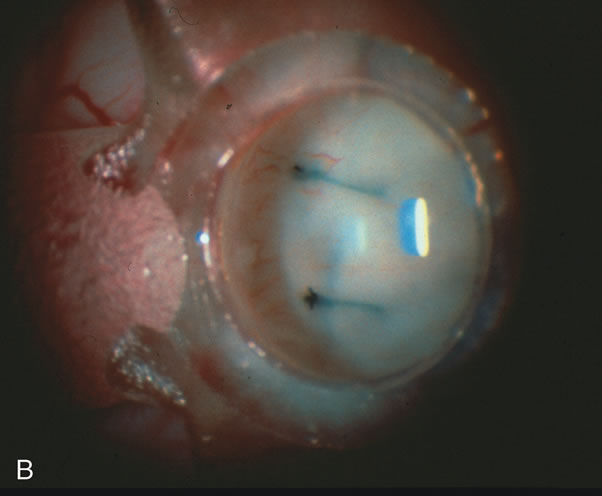

CASE 6: ANTICIPATED LENS EXTRACTION POST FAILED TRABECULECTOMY WITH ADVANCED DISC DAMAGE AND IOP OUTSIDE TARGET PRESSURE RANGE

The inflammation associated with lens extraction at any site usually causes complete failure of a marginal functioning bleb. In addition, pressure reduction by medical means is usually minimal in these recalcitrant cases, and combined surgery is indicated. In the past, these cases were approached with large-incision ECCE, clear corneal cataract incision, and bleb revision. Drawbacks included those mentioned earlier for large incision clear corneal cataract extraction, and bleb revision is often associated with conjunctival buttonholes, wound leaks, subconjunctival hematoma, destruction of friable sclera, and associated hypotony. With the advent of modern-day cataract surgery, a phacotrabeculectomy is often possible adjacent to the failed filter (Fig. 7). The ability to combine cataract extraction with implant and filtration surgery all through the same small incision has greatly improved outcomes for patients with marginal preoperative filters. There are several other viable options in this case. If the surgeon elects to remove the cataract through a temporal clear corneal incision, the bleb may be revised or a new adjacent filter fashioned. As mentioned earlier, revising a failed filter is technically challenging. If the surgeon believes it is not feasible to revise the filter or fashion a new one, a glaucoma drainage implant is a reasonable option combined with temporal lens extraction.172

Fig. 7. Phacotrabeculectomy adjacent to a failed filter in cataractous eye. The ability to combine small-incision cataract extraction with trabeculectomy all through the same incision adjacent to the failed filter allows the surgeon to work in a familiar superior area. Avoiding incisions into the existing bleb decreases conjunctival buttonholes, hypotony, operating room time, and subconjunctival bleeding. A. Appearance of failed bleb with exposure of superior temporal quadrant gained with a corneal traction suture. B. Prepare a limbus-based conjunctival flap and a scleral flap. C. This bleb is at high risk to fail again justifying the need for MMC, 0.2 mg/cc applied on a pledget for 4 minutes. D. Insert the keratome and perform phacotrabeculectomy in the usual fashion.